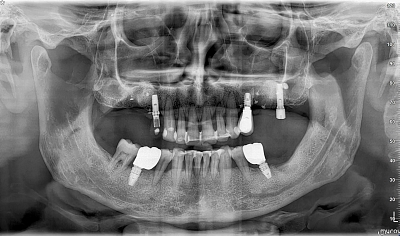

Diagnostinės galimybės

2D vaizdai

- Panoraminiai (PAN) vaizdai su keliais fokusavimo sluoksniais

- Cefalometriniai vaizdai (jei komplektacija su CEPH arm)

- Detalios žandikaulių sričių projekcijos

3D CBCT vaizdai

- SuperHD CBCT su MultiFOV funkcija nuo mažiausio (4x4) iki didžiausio (15x16) lauko

- Greitas 360° skenavimas ir mažos dozės protokolai

- Tiksli kaulinės struktūros diagnostika implantologijai, chirurgijai, ortodontijai ir ENT analizėms